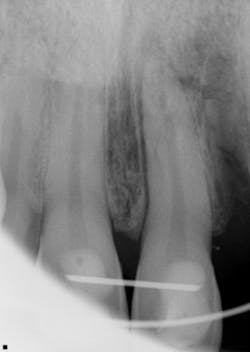

Clinical and radiographic assessment revealed the following (figure 1):

- Complete loss of tooth No. 10 (the patient did not know where the tooth went upon impact).

- Significant swelling in the maxillary and mandibular labial areas with bruising and slight lacerations on the lip and tongue, which were caused when the lower teeth impacted the maxillary teeth with the tongue in between.

- A significant lingual laceration of papilla interproximal to Nos. 8 and 9 with possible involvement of the incisive nerve. Bone exposure was evident.

- Partially avulsed and lingually displaced tooth No. 9 with Class 4 mobility. There was tissue retention only (very light and unstable).

- All other teeth mesial and distal to No. 9 appeared secure.

- Radiographic assessment revealed a horizontal fracture of the alveolar interproximal bone between Nos. 9 and 10 at the apical one-third area. Tooth No. 9 was separated from the alveolar bone with partial avulsion. It was unclear whether the root tip was fractured.

- The patient was unable to bite down due to the mobility and lingual position of No. 9.

Figure 1